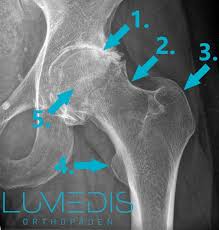

Ziehen In Der Leiste Lumedis Leistenspezialisten